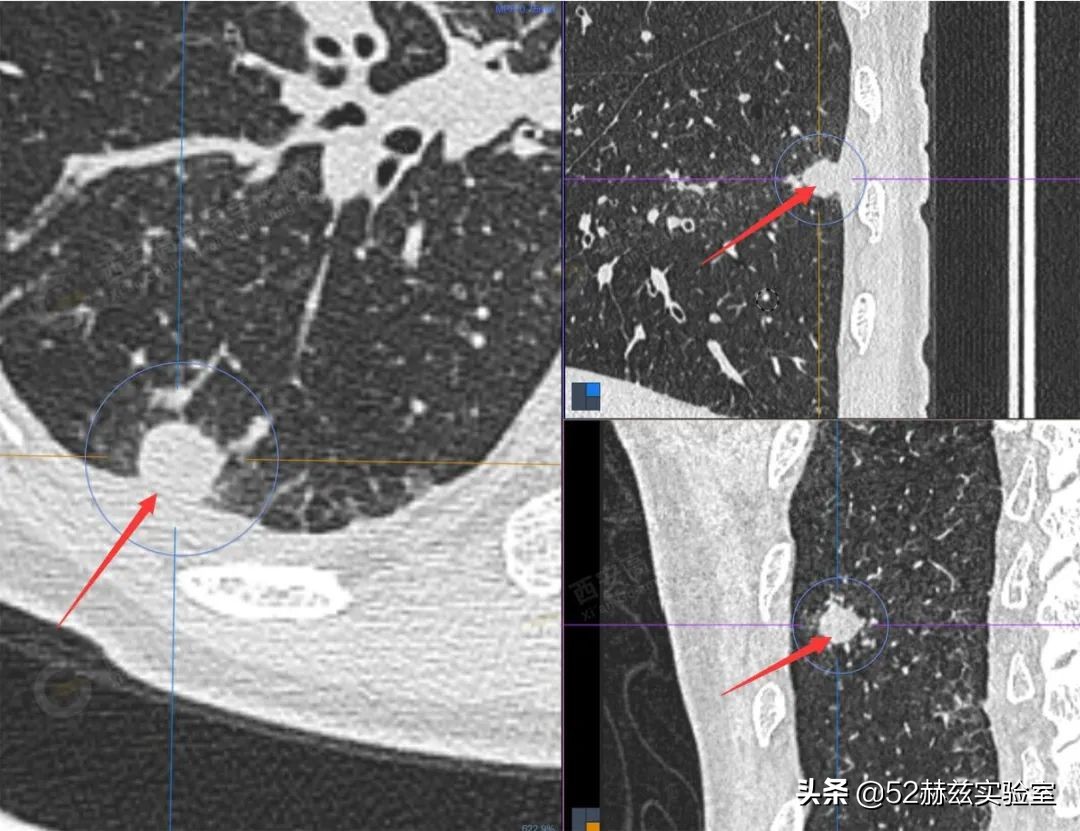

尤其是在高端医疗设备上,比如高端CT机价格通常在500万元以上。

这玩意可以提供更清晰的图像,在肿瘤等疾病诊断上面,高一个清晰度意味着能看到更详细的人体组织信息。几十个像素点的差距,就能影响医生对疾病的诊断。

由于其开发技术难度大,以至于如今80%的CT市场、90%的超声波仪器市场、90%的磁共振设备均为国外品牌所占据。